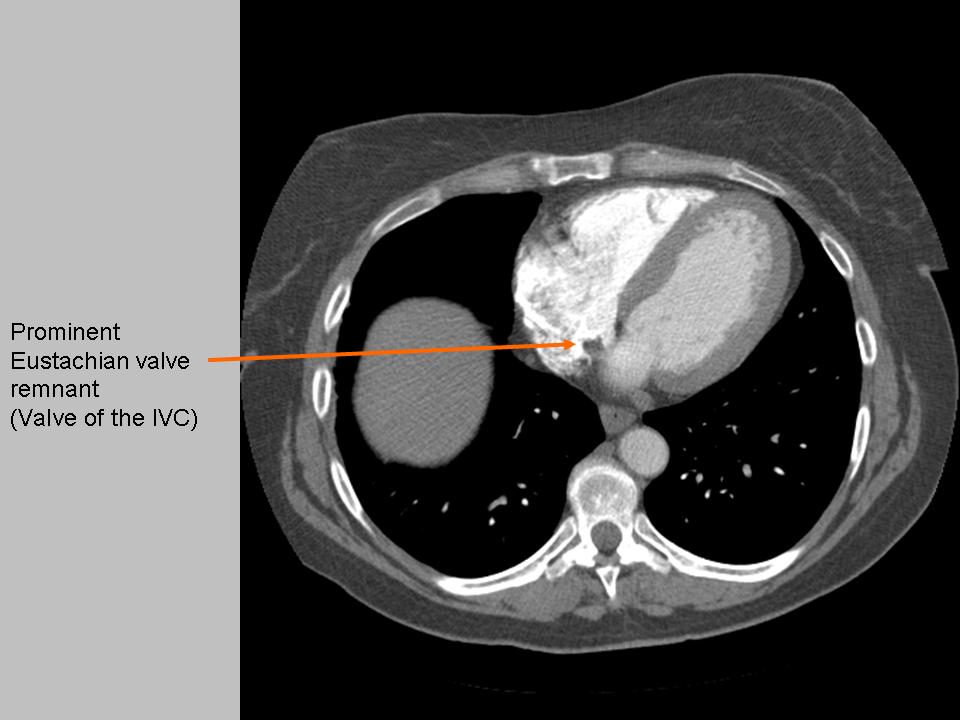

A, A prominent EV demonstrating the embryologic function of directing

Prominent Eustachian valve NephroPOCUS Valve Eustachian Function The primary function of the eustachian tube is to equalize air pressure between the atmosphere and the middle ear. The ev arises from the anterior portion of the. Yawning and swallowing cause contraction of the. The eustachian valve (ev) is an embryonic remnant of the inferior part of the right sinus venosus valve.1 following the closure of the foramen ovale. Valve Eustachian Function.